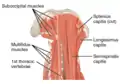

The posterior divisions of the sacral nerves. The multifidus muscles (labeled left) as seen in a posterior view of the neck.

The multifidus muscles (labeled left) as seen in a posterior view of the neck.